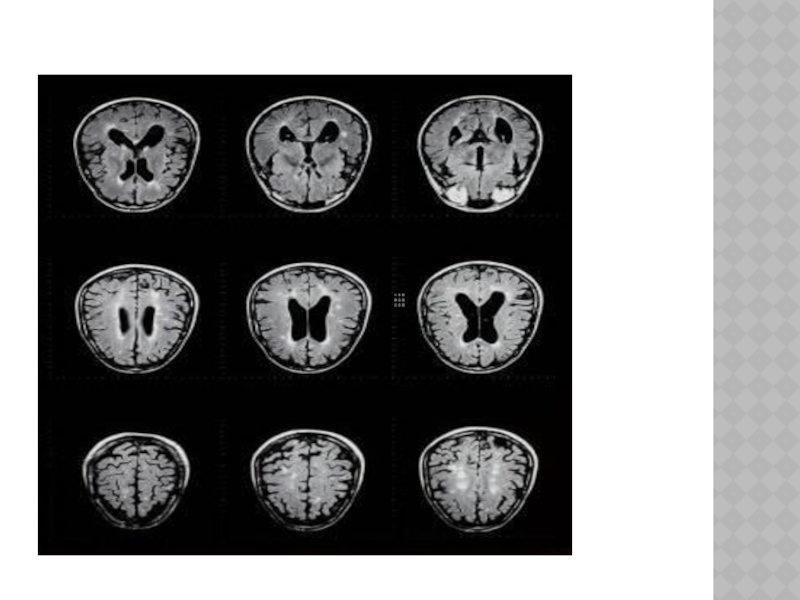

Слайд 17РАССЕЯННЫЙ СКЛЕРОЗ

Хроническое демиелинизирующее заболевание, характеризующееся признаками многоочагового поражения нервной системы, протекающее

с обострениями и ремиссиями.

Ж. Шарко в 1866 г. Частота заболевания 2-7 на 10 000 населения.

Женщины болеют почти в 2 раза чаще.

Заболевают преимущественно в возрасте от 15 до 40 лет, реже - в детском и пожилом возрасте.

РАССЕЯННЫЙ СКЛЕРОЗХроническое демиелинизирующее заболевание, характеризующееся признаками многоочагового поражения нервной системы, протекающее с обострениями и ремиссиями. Ж. Шарко

Слайд 20

В зависимости от локализации бляшек рассеянного склероза различают клинические формы заболевания:

церебральную, цереброспинальную, мозжечковую, стволовую, спинальную, а также оптическую.

Слайд 21ДИАГНОСТИКА

-анамнез(начало болезни в раннем возрасте); -обнаружение клинических симптомов, указывающих на поражения

не менее 2-3 систем (например, мозжечковой, пирамидной, глазодвигательной и др.).